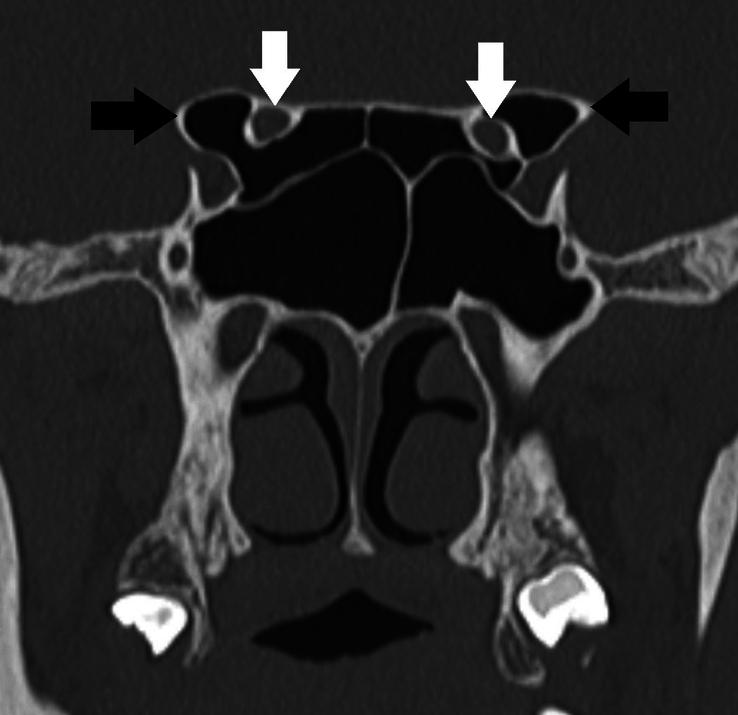

A retrospective cross-sectional study was conducted on 367 patients aged 13 years and above. Four radiologists, each with 2-6 years of experience, evaluated computed tomography scans of the PNS and the head of these patients. The optic nerves were classified into four types based on DeLano's classification, and their respective prevalence rates were determined. Additionally, the prevalence of optic nerve dehiscence and pneumatization of the anterior clinoid process was assessed.

A total of 734 optic nerves were evaluated and categorized into four groups as per DeLano's classification. The most common type was classified as type 1 optic nerve, representing 65.4% of all optic nerves. Types 2, 3, and 4 optic nerves accounted for 16.9, 8.6, and 9.1%, respectively. The prevalence rates of type 1, type 2, type 3, and type 4 optic nerves were 76.6, 24.5, 12.3, and 14.4%, respectively. Optic nerve dehiscence was observed in 14.3% of cases, with a prevalence of 21.2% in the study. Type 3 optic nerves were most commonly associated with dehiscence, with 49.2% of them showing dehiscence in their course through the ethmoid or sphenoid sinus. The prevalence of pneumatization of the anterior clinoid process in the study population was 28.3%, with type 3 optic nerves being the most frequently associated.

共评估了734条视神经,并根据德拉诺分类法分为四组。最常见的类型为1型视神经,占所有视神经的65.4%。2型、3型和4型视神经分别占16.9%、8.6%和9.1%。1型、2型、3型和4型视神经的患病率分别为76.6%、24.5%、12.3%和14.4%。在14.3%的病例中观察到视神经裂孔,在本研究中的患病率为21.2%。3型视神经最常与裂孔相关,其中49.2%在通过筛窦或蝶窦的行程中出现裂孔。研究人群中前床突气化的患病率为28.3%,3型视神经与之关联最为频繁。